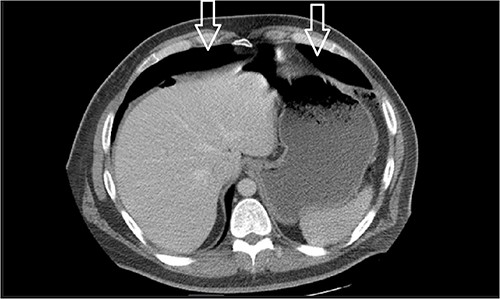

Ten days after discharge, he was readmitted with the same symptoms of nausea and vomiting. The CT showed pneumoperitoneum (see Fig. 2) again with another EL with consequent negative results and no viscus perforations. Lesser amounts of free fluid in both upper quadrants and in the pelvis were noted. These findings remain suspicious for a perforated viscus. Few days later, the patient reported feeling better and was discharged.